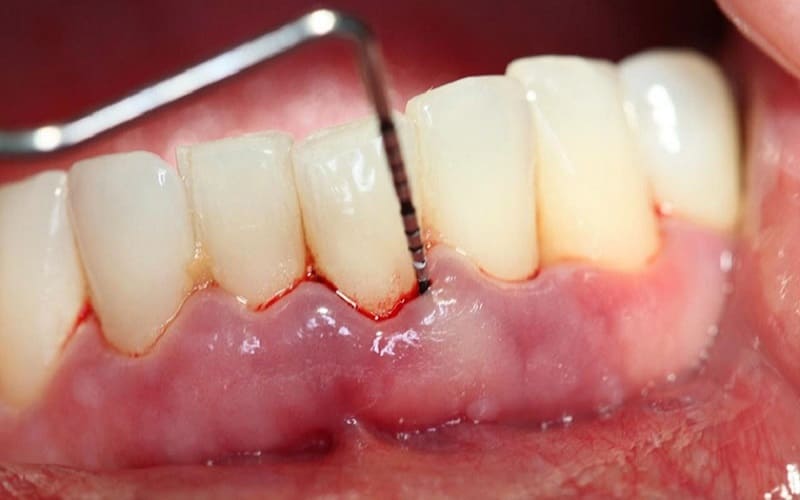

Chảy máu khi chải răng hoặc ăn nhai

Khi lợi bị tổn thương, chỉ cần tác động nhẹ như chải răng hoặc nhai thức ăn cứng cũng có thể gây chảy máu. Nếu hiện tượng này lặp lại nhiều lần, rất có thể bạn đã bị viêm lợi quanh răng sứ.